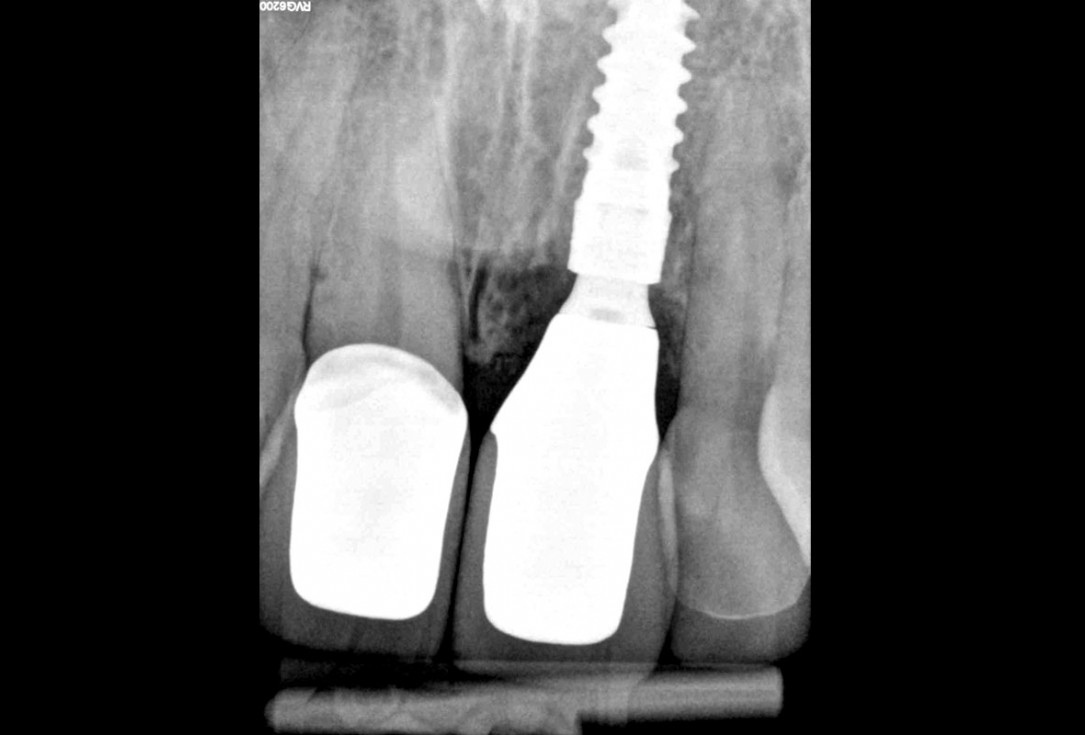

29/30 - After 1 yearExcellent aesthetic result of buccal augmentation with mucoderm® and maxgraft® after immediate implant placement - 3-years follow-up - Dr. A. Puišys

-